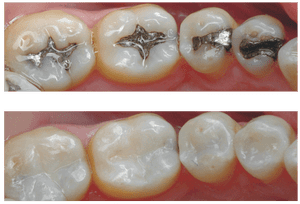

Gigi berlubang merupakan masalah yang sering membuat banyak orang merasa kurang nyaman dan bahkan sering merasa sakit gigi. Munculnya gigi berlubang bisa disebabkan oleh banyak faktor terutama kebiasaan yang kurang baik dalam merawat gigi. Ketika gigi anda mulai berlubang biasanya ketika makan akan terasa kurang nyaman dan lebih parahnya lagi gigi yang berlubang tersebut akan semakin parah dan merusak jaringan gusi. Untuk itulah banyak orang yang lebih memilih melakukan tambal gigi agar gigi yang berlubang tersebut tidak semakin parah dan masih bisa digunakan untuk mengunyah makanan.

Gigi berlubang perlu dilakukan penambalan sesegera mungkin untuk menghindari lubang yang bertambah besar dan dalam. Jika lubang sudah terlalu dalam hingga menembus saraf gigi maka harus dilakukan Perawatan Saluran Akar (PSA) dengan beberapa kunjungan. Jika lubang sudah terlalu besar dan tidak bisa di tambal, maka dengan terpaksa dilakukan pencabutan gigi.

Tentunya PSA dengan beberapa kunjungan sangat menyita waktu. Pencabutan gigi pun sangat merugikan karena kehilangan gigi dan harus membuat gigi tiruan sebagai pengganti dengan biaya yang tidak murah. Jika saat ini para pembaca merasa ada gigi yang berlubang segeralah kunjungi dokter gigi